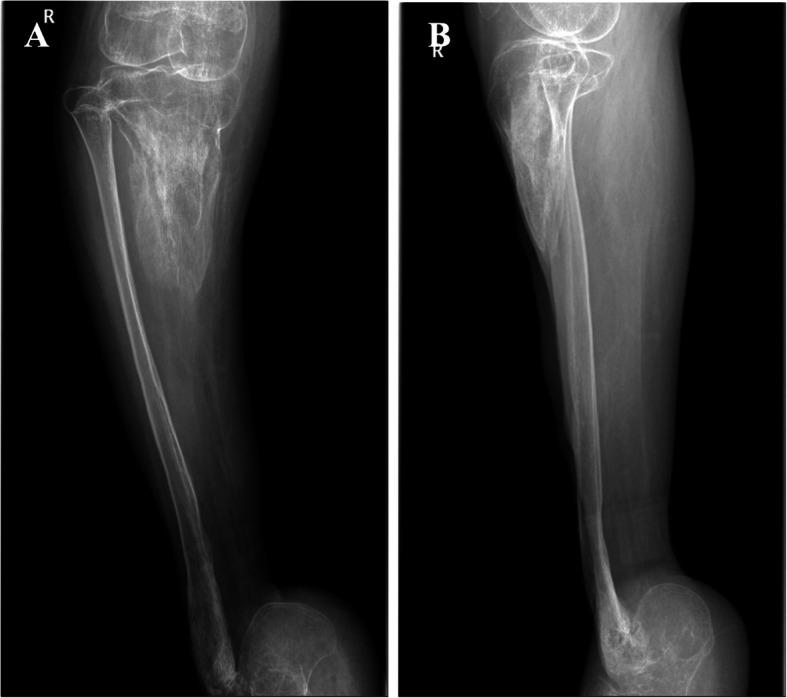

A 16-year-old male patient fell and injured his right lower leg. He attempted to treat the symptoms with traditional home remedies. During 15 months of self-treating, he developed osteomyelitis of the right tibia and had lost function in his foot. Radiology revealed immense bone defect of the right tibia, including talus bone defect and equinus deformity of the calcaneus. The patient's right tibia was non weight-bearing, had drainage sinus just below his knee and a large scar anteriorly along the entire length of the tibia.

一名 16 岁男性患者因摔倒致右小腿受伤。他试图用传统的家庭疗法治疗症状。在 15 个月的自我治疗期间,他患上了右胫骨骨髓炎,足部功能丧失。影像学检查显示右胫骨存在巨大的骨缺损,包括距骨骨缺损和跟骨马蹄内翻畸形。患者的右胫骨不能承重,膝关节以下有引流窦道,胫骨前全长有一个大疤痕。